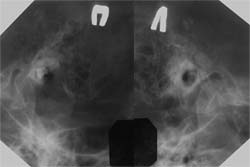

Ангиография является обязательным исследованием при подозрении на гломусную опухоль. Благодаря этому исследованию определяется не только локализация и распространенность хорошо кровоснабжаемого образования, но и выявляются первично множественные гломусные опухоли (Рис. 4). Ангиография позволяет провести дифференциальную диагностику между гломусной опухолью и другими новообразованиями расположенными в области яремного отверстия и имеющими схожие признаки на КТ. Другие опухоли, не имеющие такую выраженную кровеносную сеть, при ангиографии не визуализируются.

[Увеличить]

Рис. 4. Ангиограмма. Множественные параганглиомы